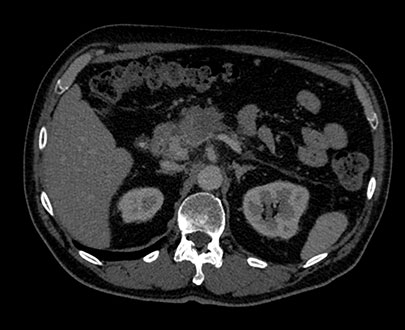

MonoE zakresie 75keV

Suwak wyboru energii 75kev

Badanie MonoE pozwala uzyskać zsyntetyzowane obrazy monoenergetyczne przy wstępnie zdefiniowanych wartościach w zakresie od 40 keV do 200 keV. Wygląd obrazów zmienia się wraz ze zmianą wartości keV, nawet jeśli ustawienia okna/poziomu są takie same. Przykładowo przy niższych wartościach keV jod może wydawać się jaśniejszy, natomiast wyższe wartości keV pozwalają ograniczyć artefakty pochodzące od metalowych implantów.